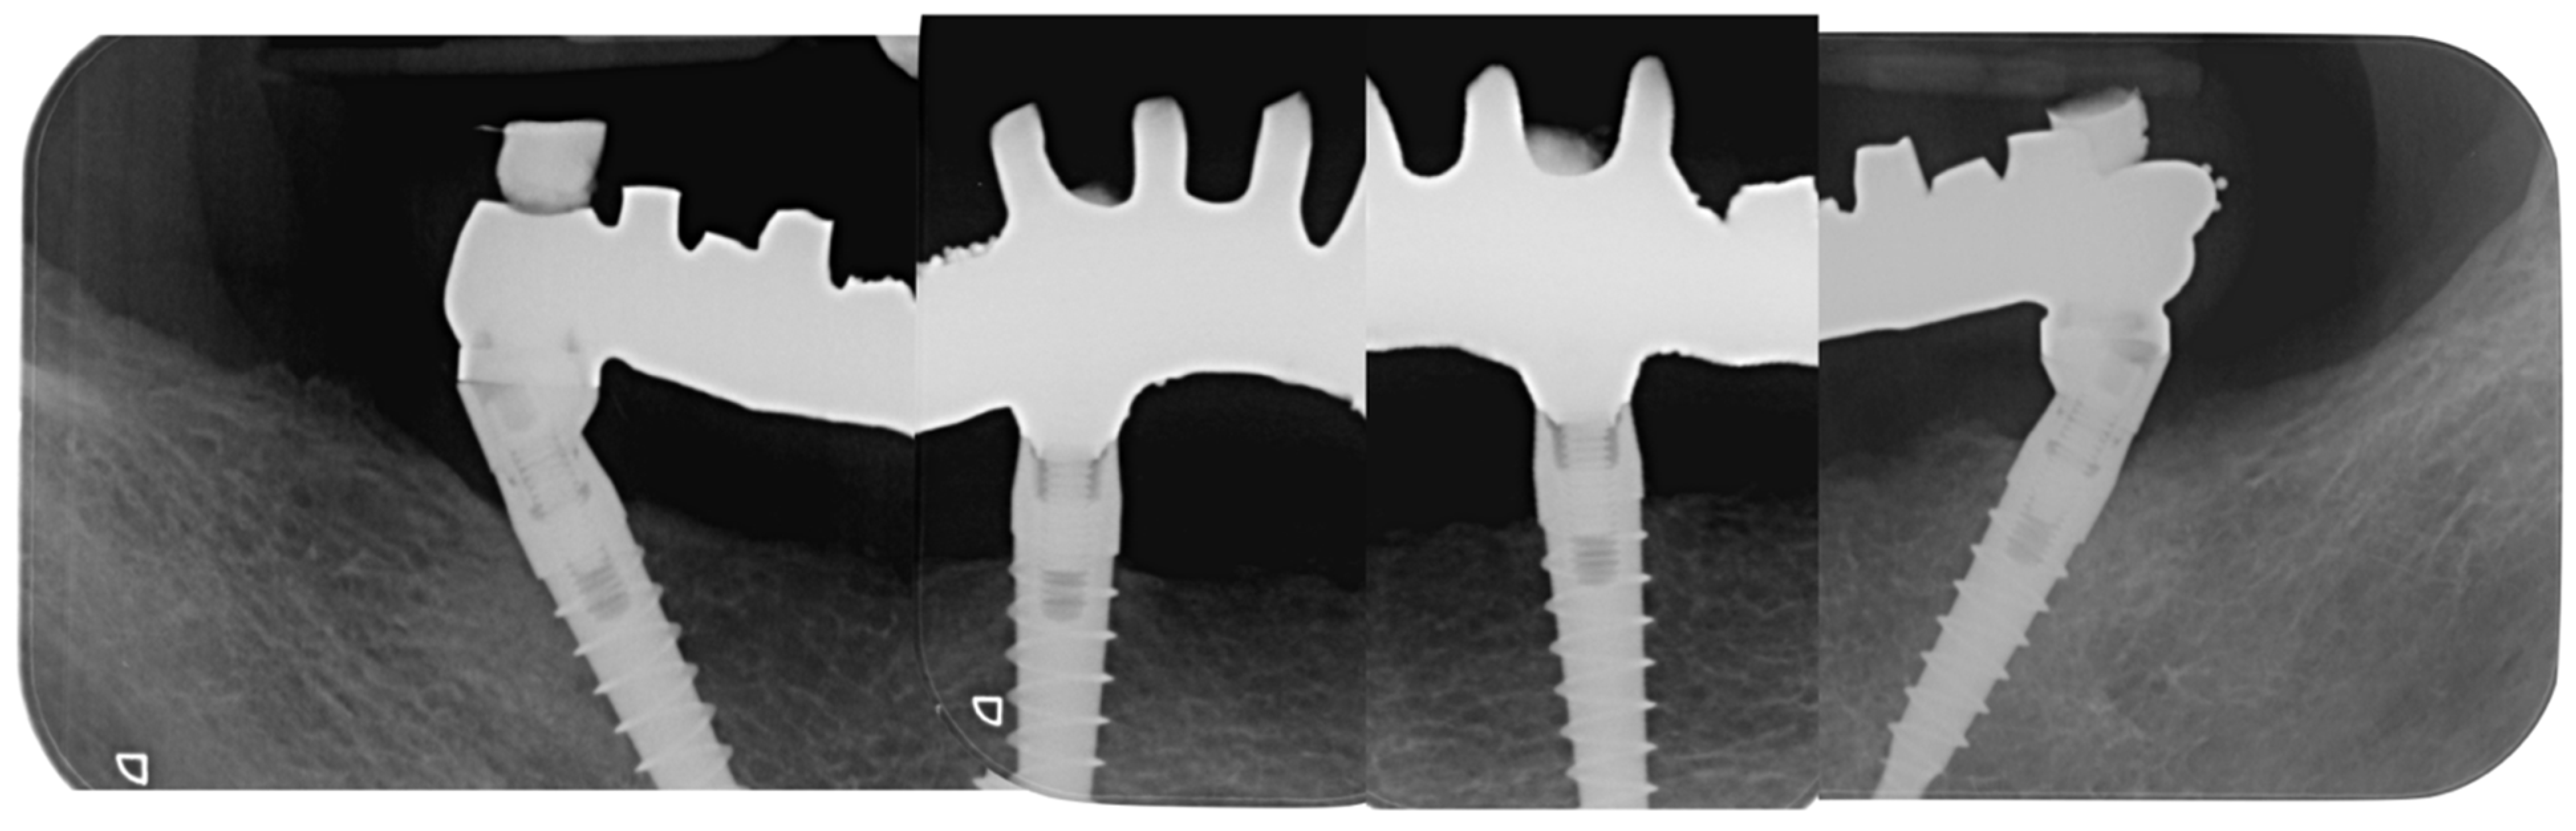

3. Results

- Probing depth (mm): Distal right (DR) implants showed 2 mm probing depth on the mesial side, 2 mm on the vestibular side, 3 mm on the distal side, and 3 mm on the lingual side. The anterior right (AR) implant showed 3 mm probing depth on the mesial side, 3 mm on the vestibular side, 2 mm on the distal side, and 3 mm on the lingual side. The anterior left (AL) implant showed 2 mm probing depth on the mesial side, 2 mm on the vestibular side, 3 mm on the distal side, and 3 mm on the lingual side. The distal left (DL) implant showed 2 mm probing depth on the mesial side, 2 mm on the vestibular side, 3 mm on the distal side, and 3 mm on the lingual side.

- Bleeding on probing (BOP): DR, AR, and DL implants presented one side each with BOP. No BOP was detected on the AL implant.

- No plaque was detected at any sites.